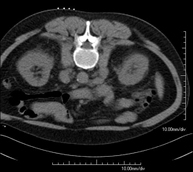

- Abdomen CT

Diagnostic test that involves obtaining high-definition anatomical images of the abdomen (liver, gallbladder, bile duct, pancreas, spleen, stomach, intestines, kidneys, vascular structures, bladder, uterus and ovaries, etc.) using CT (computed tomography) equipment. These images are then studied at a workstation capable of producing two-dimensional reconstructions in different spatial planes, and also 3D (volumetric) reconstructions. Most studies require the use of iodinated contrast to improve image definition.

- Abdominal and pelvic CT

Diagnostic test that consists of obtaining high-definition anatomical images (bone structures, vascular structures, liver, pancreas, gallbladder, kidneys, adrenal glands, spleen, small and large intestine, bladder, uterus and ovaries, prostate and seminal vesicles, ureters, etc.) using CT (computed tomography) equipment. Most studies require the use of iodinated contrast.